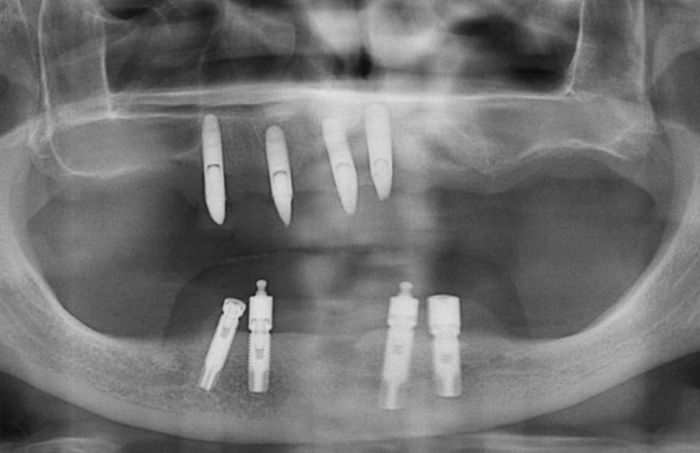

Imagens após remoção dos dentes e do implante comprometido